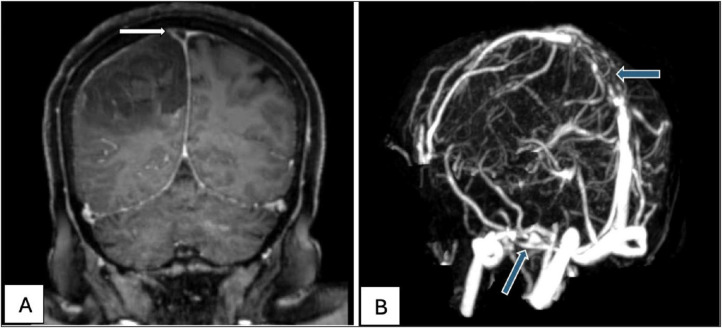

Case presentation: We report a unique case of CVST induced by HIT in a patient with an established diagnosis of MG. Following plasma exchange therapy, which included heparin administration, the patient developed symptoms indicative of CVST. Diagnostic imaging confirmed thrombosis in the cerebral venous sinuses. Management involved the immediate discontinuation of heparin and the initiation of fondaparinux, leading to effective anticoagulation and clinical improvement.

Abstract Image